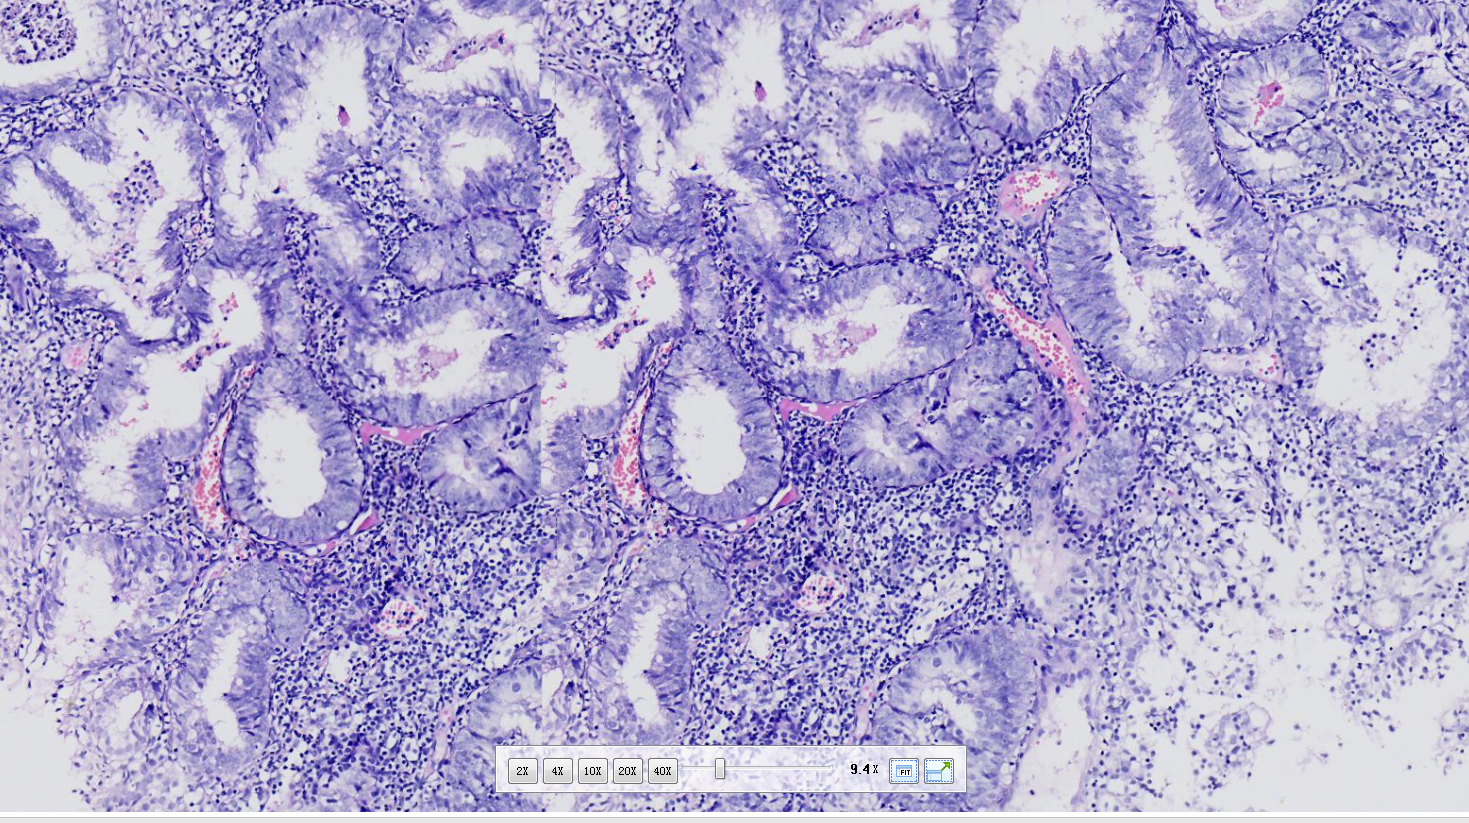

性别

女

年龄

62岁

不规则出血半年

子宫内膜(刮宫)

灰红软组织一堆,体积0.5*0.4*0.3cm。

临床情况:月经史?之前有无诊刮及诊断?有无用药?内膜呈高分泌相改变,部分腺体呈非典型增生改变。

非典型性子宫内膜增生。